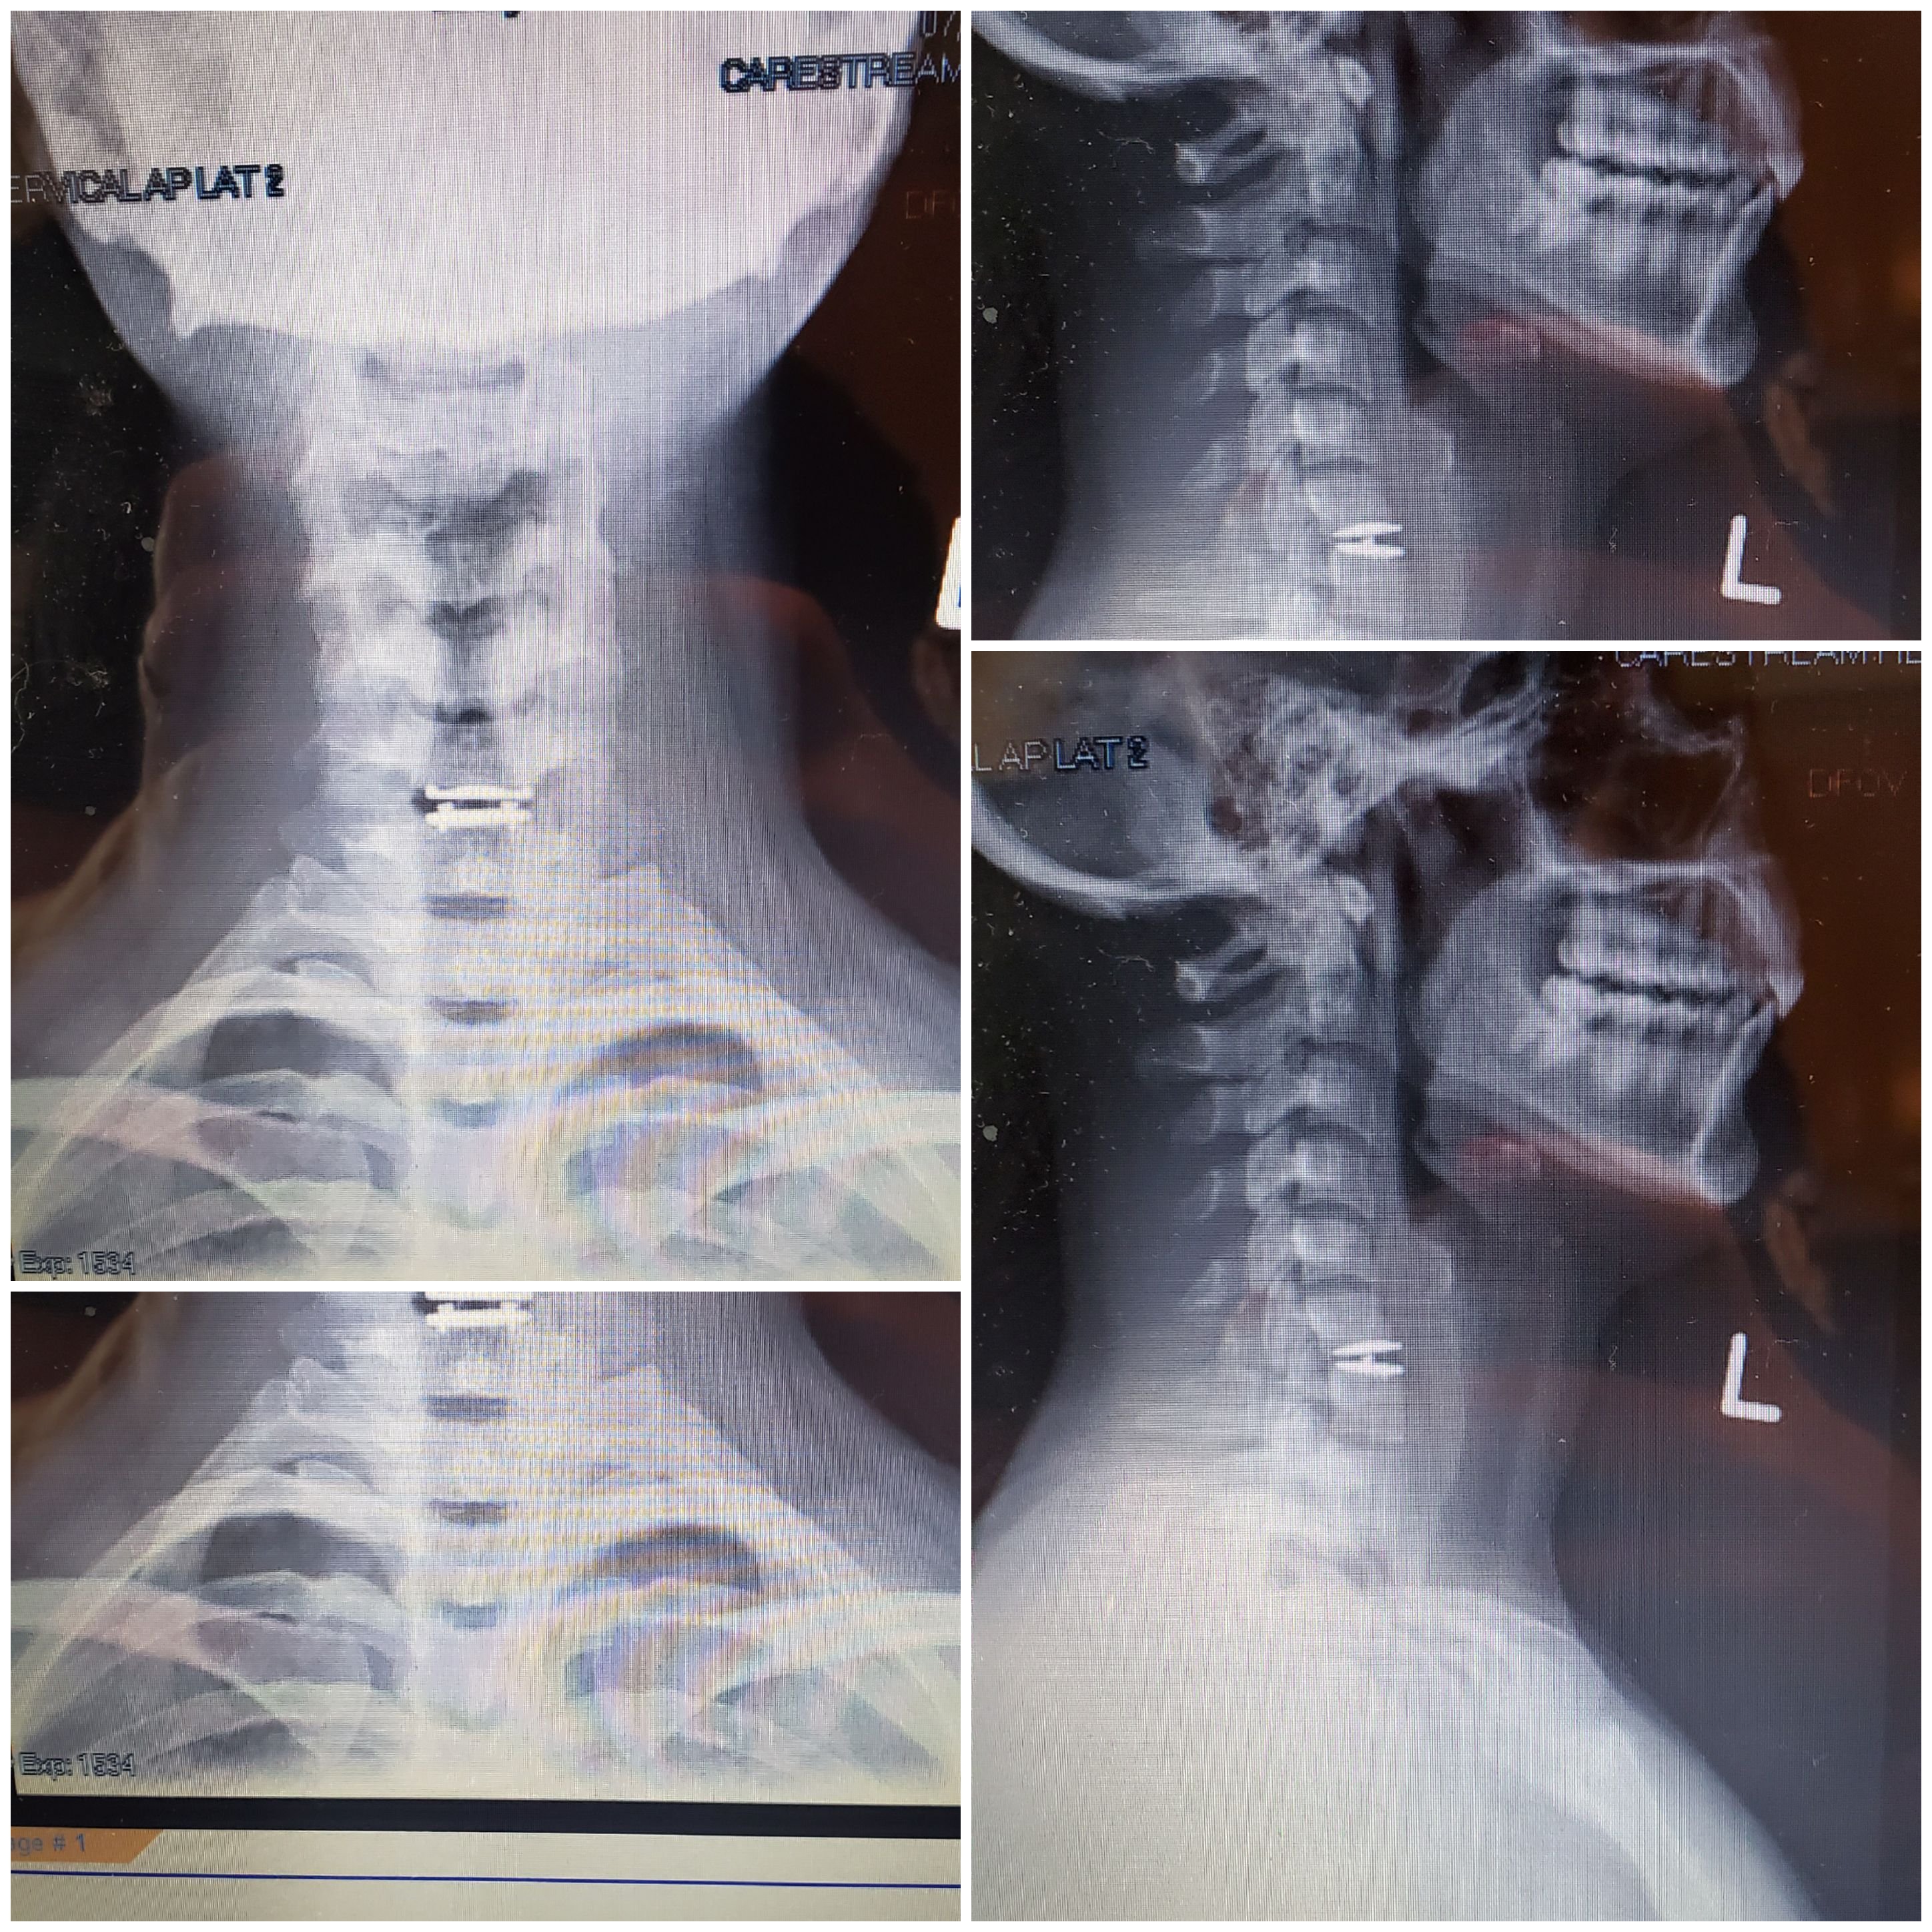

I continued to knock on the doors of the medical field, desperate to find a permanent answer for temporary pain. The victory came, when the pain management doctor ordered another EMG and my pain was finally validated on paper! I was never happier to see that there was evidence of nerve damage on a document. I googled everything, which you shouldn’t do by the way. But I learned more than I care to know about the human body. The little bulge on the MRI caused muscle atrophy, to the extent that my shoulders became uneven. I compensated on my left for my right was lacking.

Now with the documentation in hand, I was faced with the decision to pursue surgery. Not just any, it was my spine! My neck! One of the most vulnerable places on your body. I was scared, yet I prayerfully continued moving forward. I already saw 2 surgeons , who denied me and said the pain was not nerve related. That basically, I had to learn to live with it. That was completely unacceptable! They made me feel like I was crazy! So I set my prayerful path to find a surgeon, not knocking on one door, but several. I read reviews, researched and became my own advocate and had to stay in network because let’s face it, money is the bottom line!

My husband Angel and I went together and sat patiently waiting of the verdict. This doctor was different. He was meek, compassionate and self assured. He patiently went through the MRI and examined it with a fine tooth comb. I wasn’t prepared for his response, but he had the solution. He walked us through the MRI and even acknowledged how it could have been overlooked. He blew up the image and showed us where the nerve root exited and how it was encroached by the “minimal disc protrusion” He offered two solutions; an artificial disc replacement or a fusion. I asked what he recommended and he suggested the ADR because it preserves the natural motion of the spine and doesn’t cause the discs above and below to be jeopardized. I was shocked and afraid, but signed the papers none the less to move forward. I came to the absolute end of myself to manage pain and signed up to fix the root of the problem. I was afraid and angry with God because I knew that he could fix me, I had no doubt. We don’t get to decide how God chooses to heal us, but sometimes we have to take the hard road.